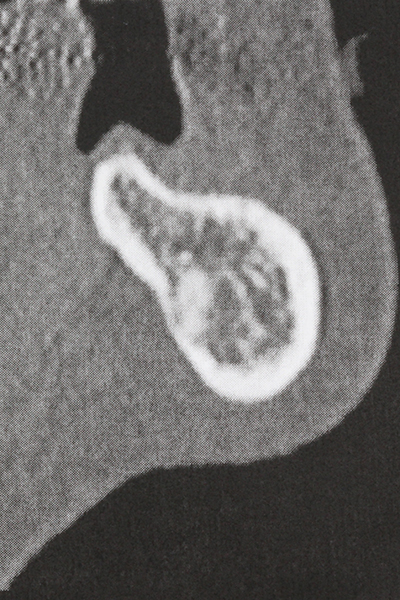

When surgical procedures are performed on bone in the immediate vicinity of sensitive structures such as blood vessels or nerves, rotary instruments pose a significant risk of iatrogenic injury. Piezoelectric devices can be helpful for preparation of bone covers and removal of hard tissue close to nerves, particularly for exposure of nerves after iatrogenic injury but also during nerve lateralization for resective and reconstructive procedures or implant placement (Fig. 17-20). Light contact between the piezotip and the nerve does not generally result in damage but proceeding incautiously with saw-like motions or attachments where a residual bone substrate remains may cause temporary or even permanent nerve damage. However, the risk of damage is considered to be substantially lower than when using saws or milling instruments (Pereira, Gealh et al. 2014).